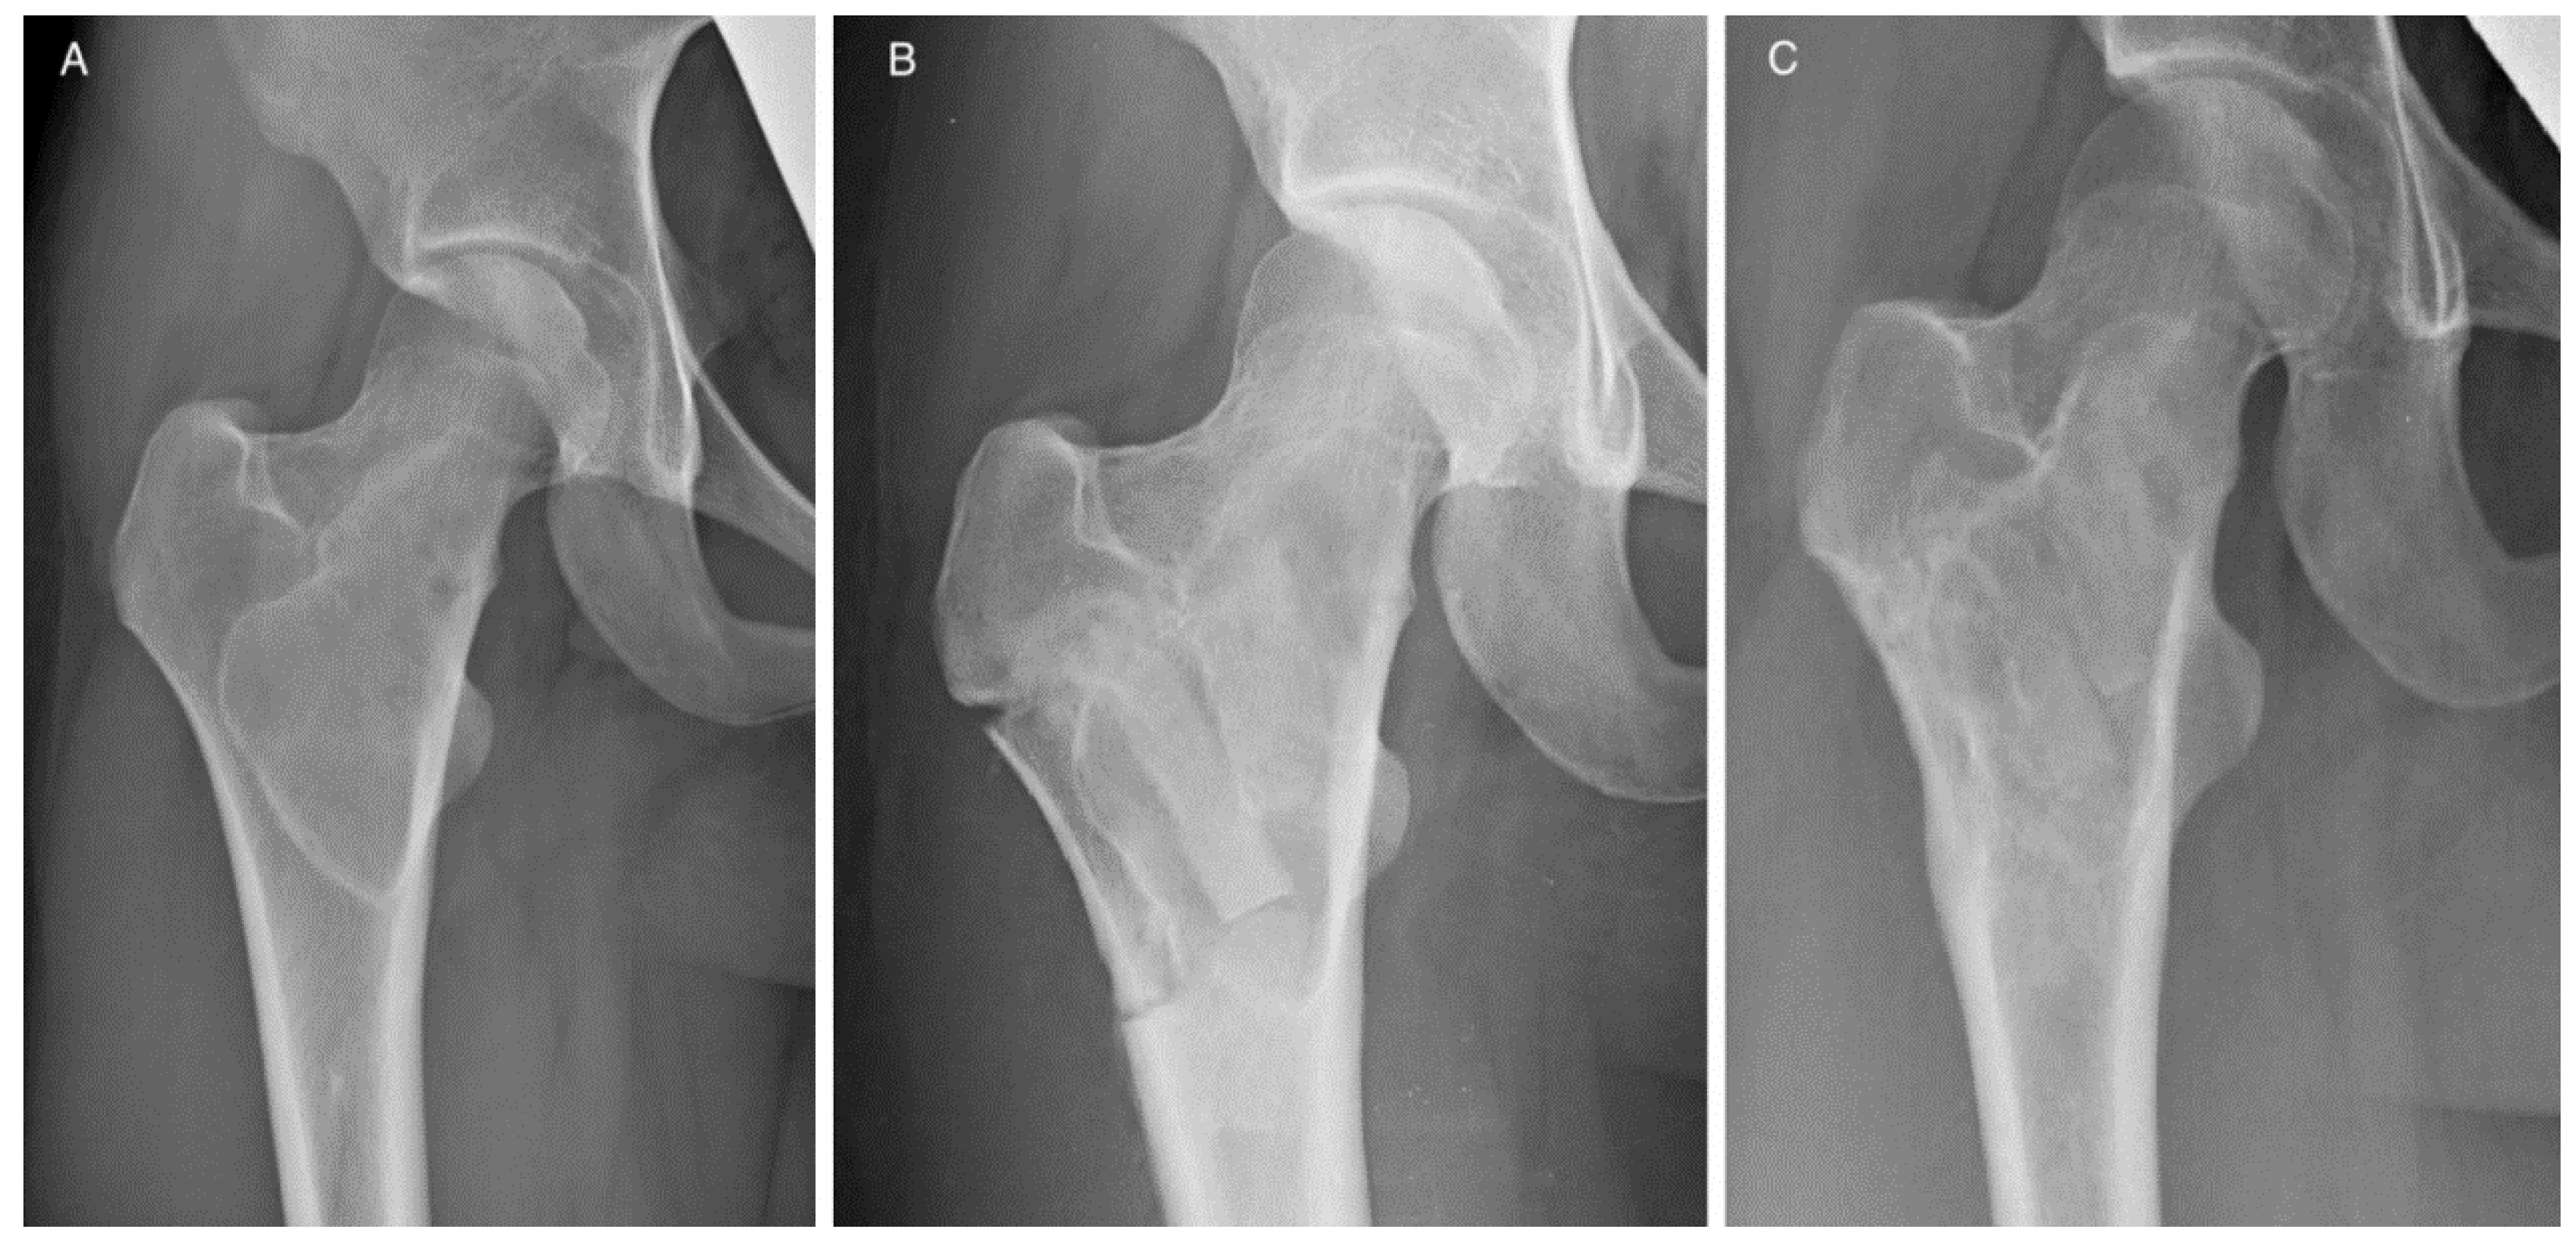

The handling and workability of this biomaterial and its mechanical properties were known, as they were previously investigated in vitro [20,37] and assessed in clinical applications [19,36,37]. Moreover, complex cases were also investigated in silico [38] in order to determine biomaterial limits under extreme loads. These evidences, together with the analysis of each case here reported (see Table 2), allowed for early weight-bearing and avoiding a preventive bone fixation in most of the patients. Only in four cases was bone stabilization necessary because for three of them more than two thirds of the cortical circumference of the tibia or femur were involved, in patients with a relevant Body Mass Index. In the other case, an extensive cortical resection was performed. In some specific cases, the positioning of SB blocks longitudinally along the major mechanical axis of the bone may give the opportunity to obtain higher stability [38]. The radiological evaluation of the graft integration was good or excellent according to Mosetto’s six-grade score in 95% of the sample (20 out of 21 patients). Figure 2 shows the progressive optimal integration of SB after curettage of a proximal femur Fibrous Dysplasia. The poor result was in the patient with myxofibrosarcoma, where the SB blocks were used to reconstruct the lateral cortex of the humerus. In this case, the radiolucent line surrounded the whole graft, which was also partially reabsorbed (Figure 3). At the same time, no major complications occurred. The risk for recurrence is related to the characteristics of the disease and the performed curettage. A more aggressive curettage, if indicated, can also increase local bleeding and help bone healing and graft integration. This product appeared valid and safe not only in benign bone diseases. The case of recurrence occurring to the patient with patellar GCT initially presented an interruption of the anterior patellar cortex and an involvement of the surrounding soft tissues. An inadequate lesion removal may have caused an early relapse and progression of the disease, but as seen on the MR scan and intraoperatively, an important disease dissemination occurred in the host tissue. On the contrary, the SB block previously implanted was still intact and was not invaded by pathological tissue. Such preliminary results may suggest that SB does not help vehiculate the disease.

Figure 2. Patient 19. (A) Proximal right femur Fibrous Dysplasia. Radiological evolution after curettage and SB grafting with shaped blocks after (B) 3 and (C) 6 months of follow up.